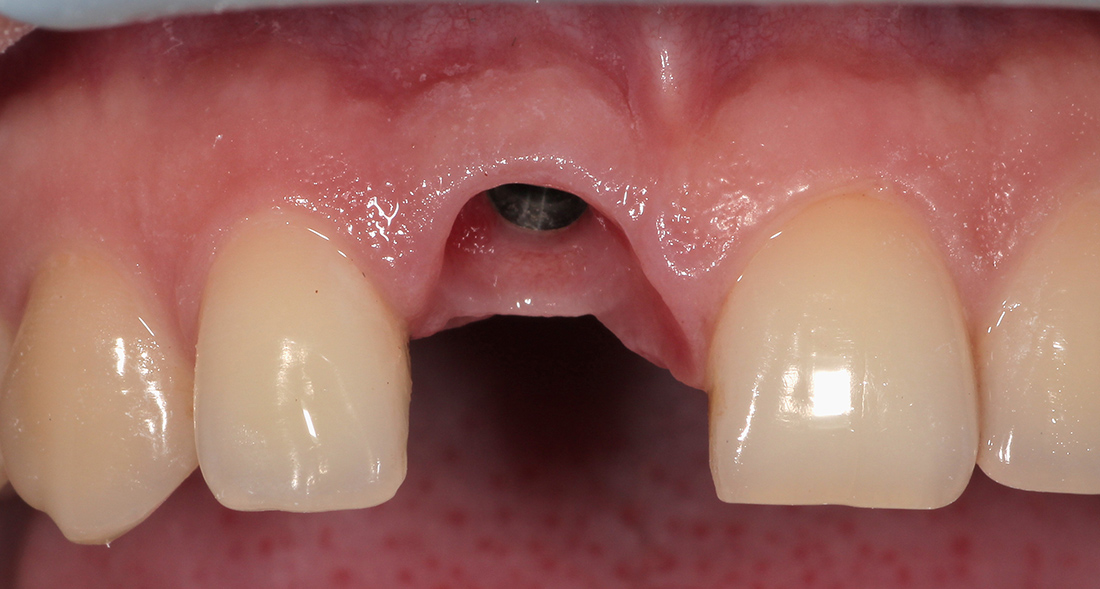

Под местной анестезией был удален зуб, установлен имплант, проведена пластика мягких тканей и фиксирована временная коронка. Через три месяца проведена оценка импланта, и мы перешли к замене временной коронки на постоянную. Опорой для коронки на импланте послужил индивидуальный циркониевый абатмен.

Для закрытия диастемы- промежутка между центральными зубами, было решено дополнительно изготовить винир на соседний зуб. Коронка и винир были изготовлены из цельнокерамического материала E.Max Press, позволяющего создать наиболее естественные и эстетические реставрации. Фиксация ортопедических конструкций была проведена за один этап.

Финальным результатом лечения остались довольны и пациентка, и мы.